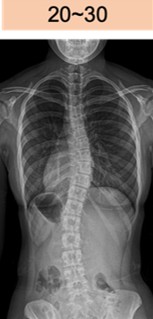

コブ角 20-30度

20~30°

思春期特発性側弯症は、骨の成長期に急速に進行する可能性があり、3〜6ヶ月ごとの頻回な経過観察が推奨されます。しかし、現状の標準検査であるX線撮影は放射線被ばくを伴うため、放射線感受性の高い若年層への頻繁な使用は避けたいというジレンマが生じ、最適なタイミングでの介入を困難にしています。